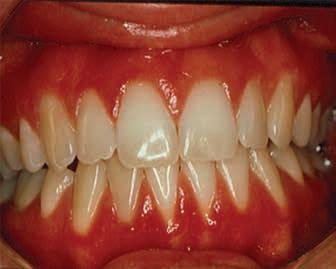

Mucous Membrane Pemphigoid

Mucous membrane pemphigoid (MMP) is an autoimmune blistering disorder that affects the oral and/or other mucosal surfaces. It affects women twice as often as men and occurs most frequently in the 5th to 7th decades of life.2 Clinically, MMP presents as desquamative gingivitis (bright red gingiva) often showing a positive Nikolsky’s sign (sloughing of the outer surface of the oral mucosa with slight rubbing) (Figures 3-5).

Figures 3-5. Mucous membrane pemphigoid (MMP) presenting as desquamative gingivitis; poor plaque control resulting from the inability to brush comfortably; patient responded well to topical steroids applied in delivery trays. Figure 3 Figure 4 Figure 5

Vesiculobullous lesions occasionally occur on other mucosal surfaces such as the conjunctiva, genitals, skin, nares, esophagus, urethra, and rectum. Symblepharon formation (scarring extending from the conjunctiva to the eyeball itself) can lead to blindness (Figure 6). It is wise to refer patients for an evaluation by an ophthalmologist following diagnosis. Biopsy for routine histology and direct immunofluorescence is often necessary for a definitive diagnosis. Specimens will show a clean, sub-basilar separation of the epithelium from the underlying connective tissue.

Treatment of MMP usually begins with medications and techniques previously described for oral lichen planus— topical and/or systemic steroids applied via various techniques. Systemic therapy with doxycycline or dapsone has shown value in the management of patients with MMP along with other medications which are prescribed by physicians due to their complex side-effects and monitoring demands. More recently, biologics have been used in patients who have not responded to more conventional therapy or have high-risk side effects.